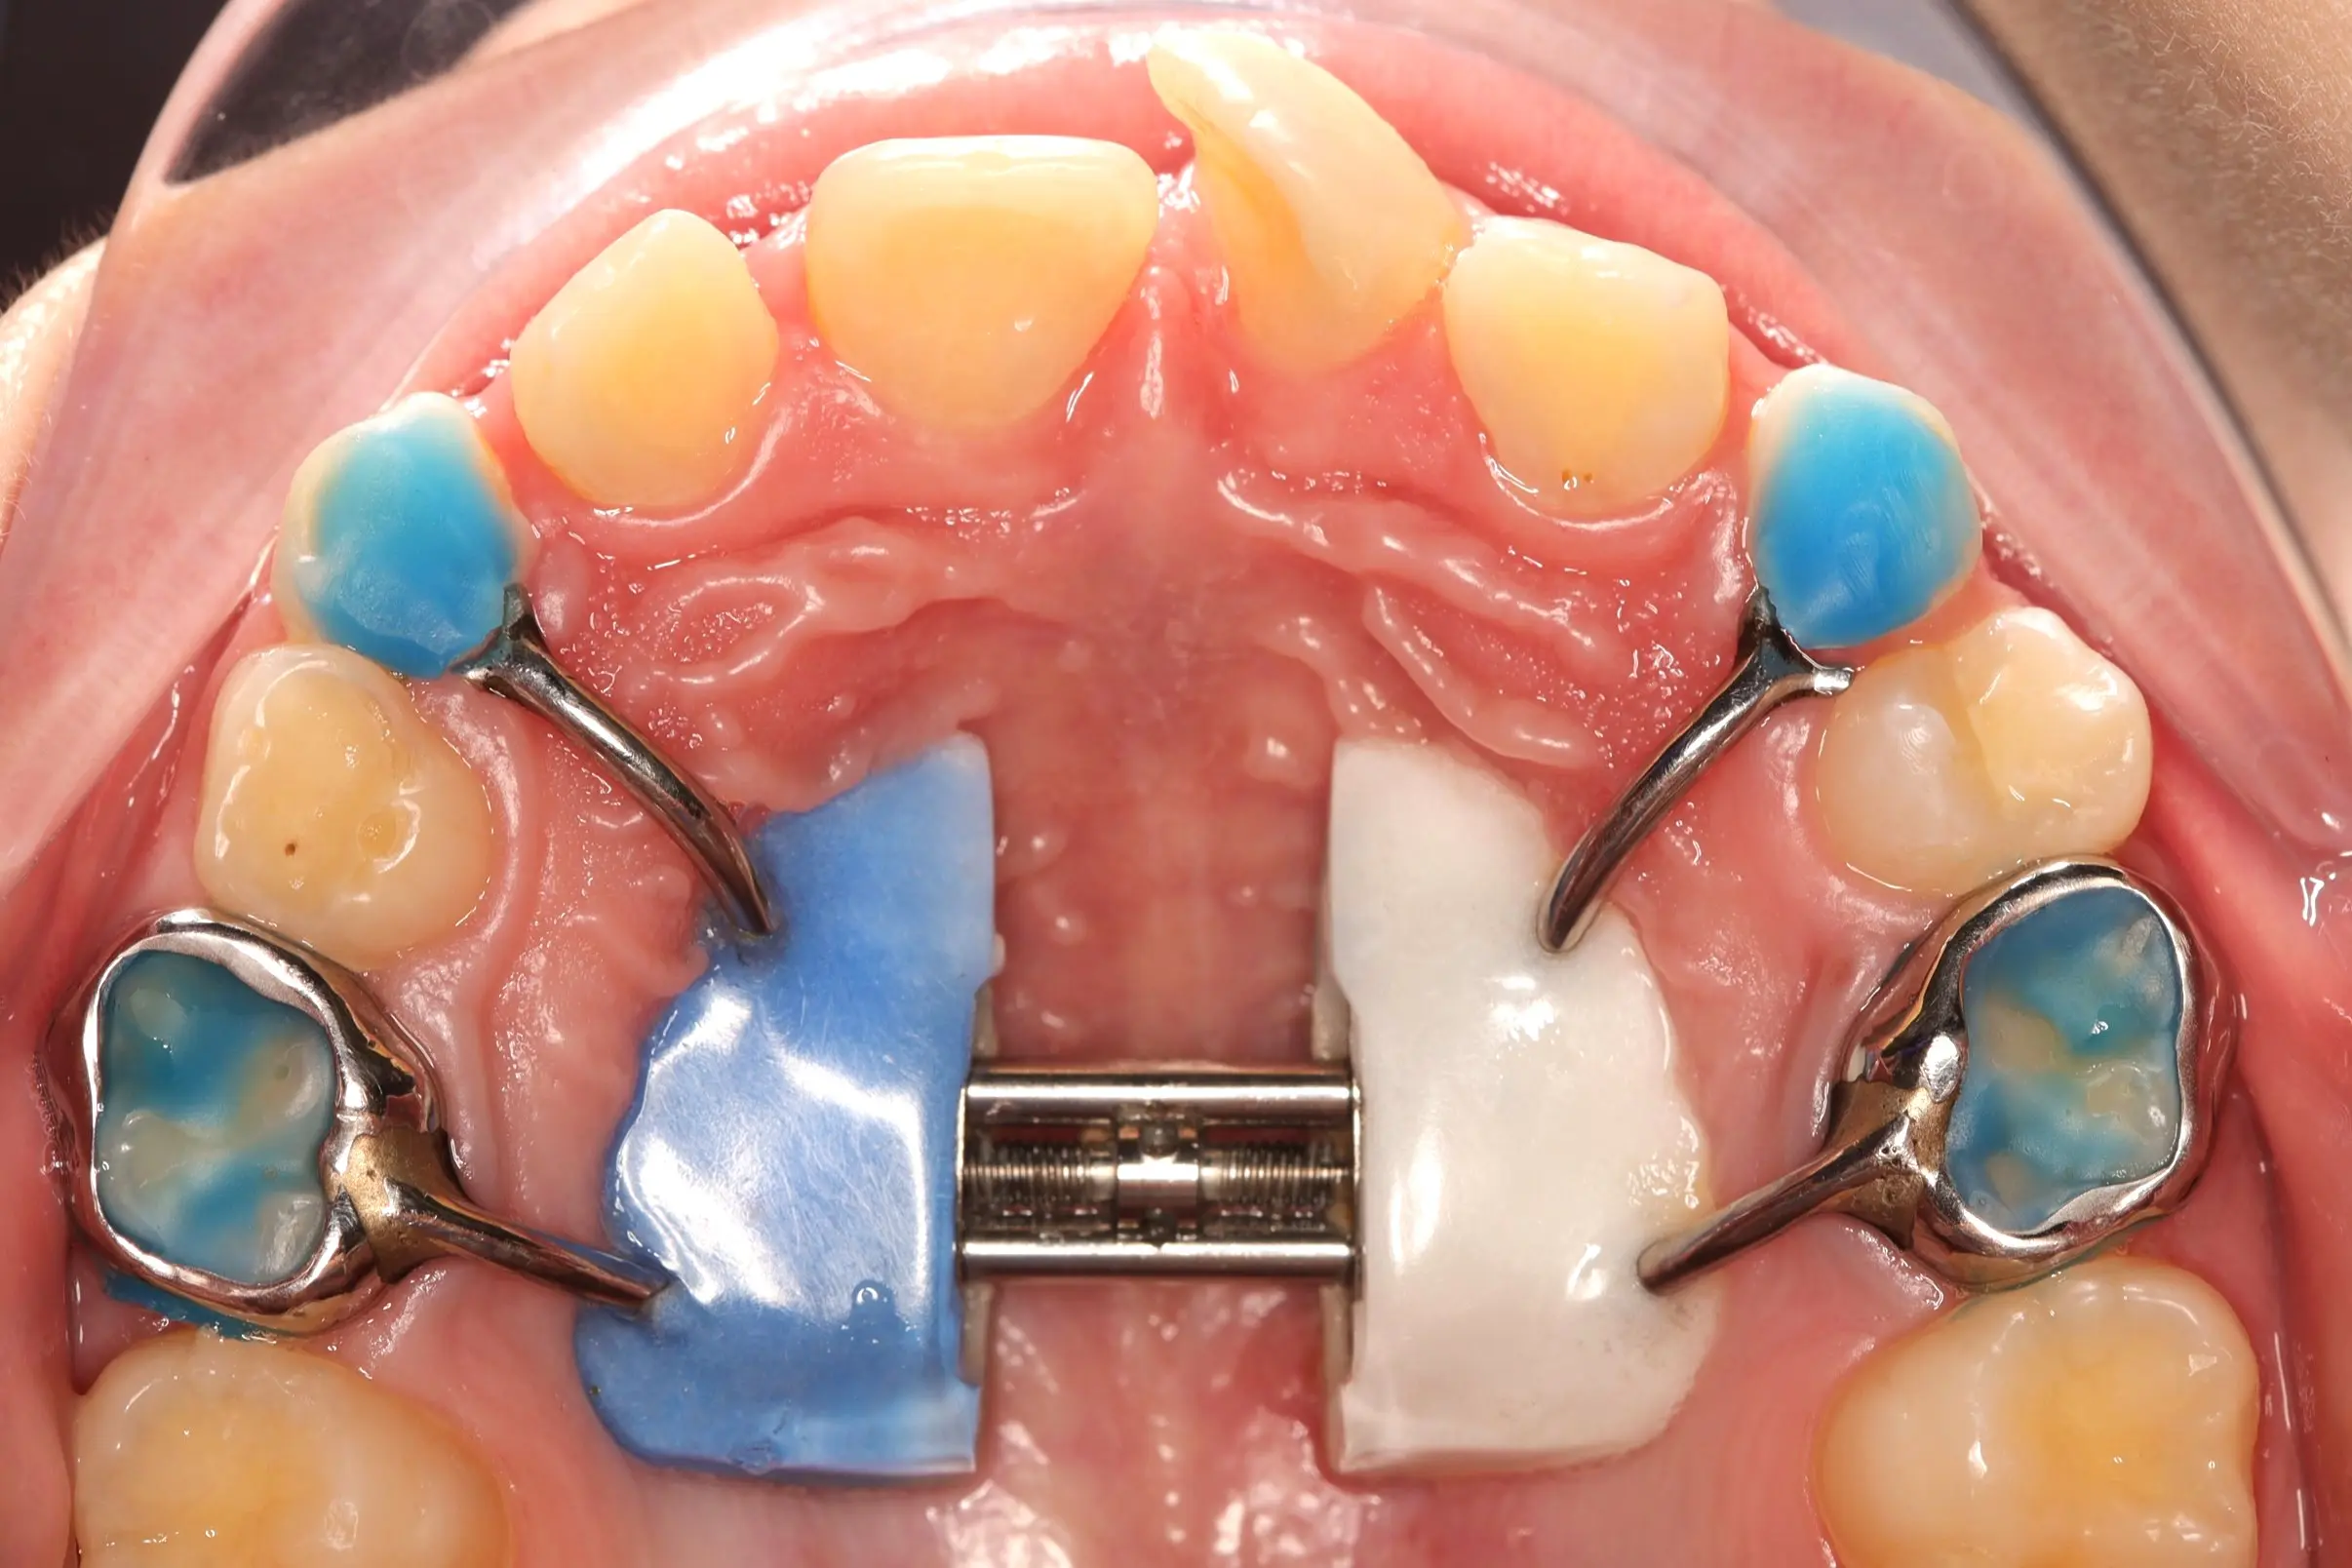

Лікування розпочато з розширення верхньої щелепи за допомогою незнімного апарату Marco Rosa, що дозволило сформувати необхідний простір. Далі проведена корекція положення різців із використанням часткової металевої брекет-системи 2х4, яка забезпечує точний контроль навіть на ранніх етапах формування прикусу.